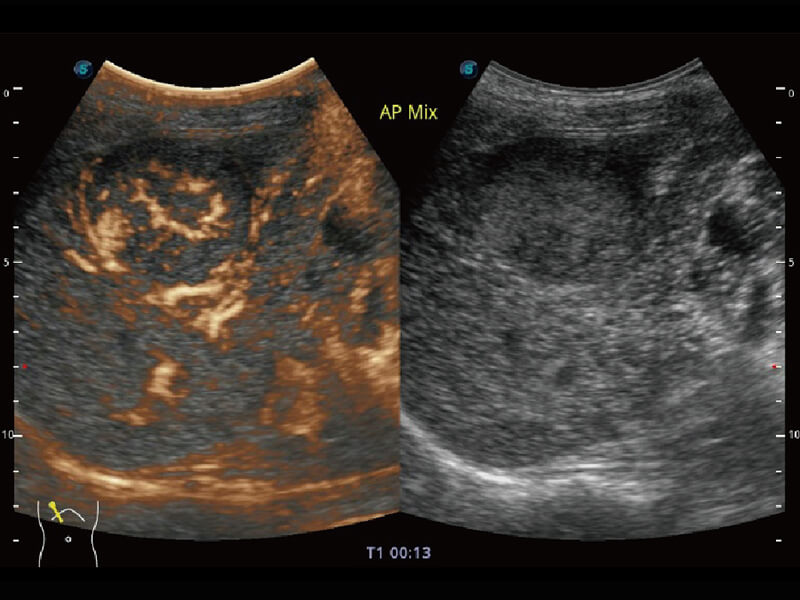

Micro F 显微血流成像 明察秋毫

高分辨率容积成像 栩栩如生

超宽频带技术,为容积成像带来优质的二维图像基础,为您呈现丰富的结构细节,栩栩如生地展示宝宝的宫内形态以及各种组织的立体结构。